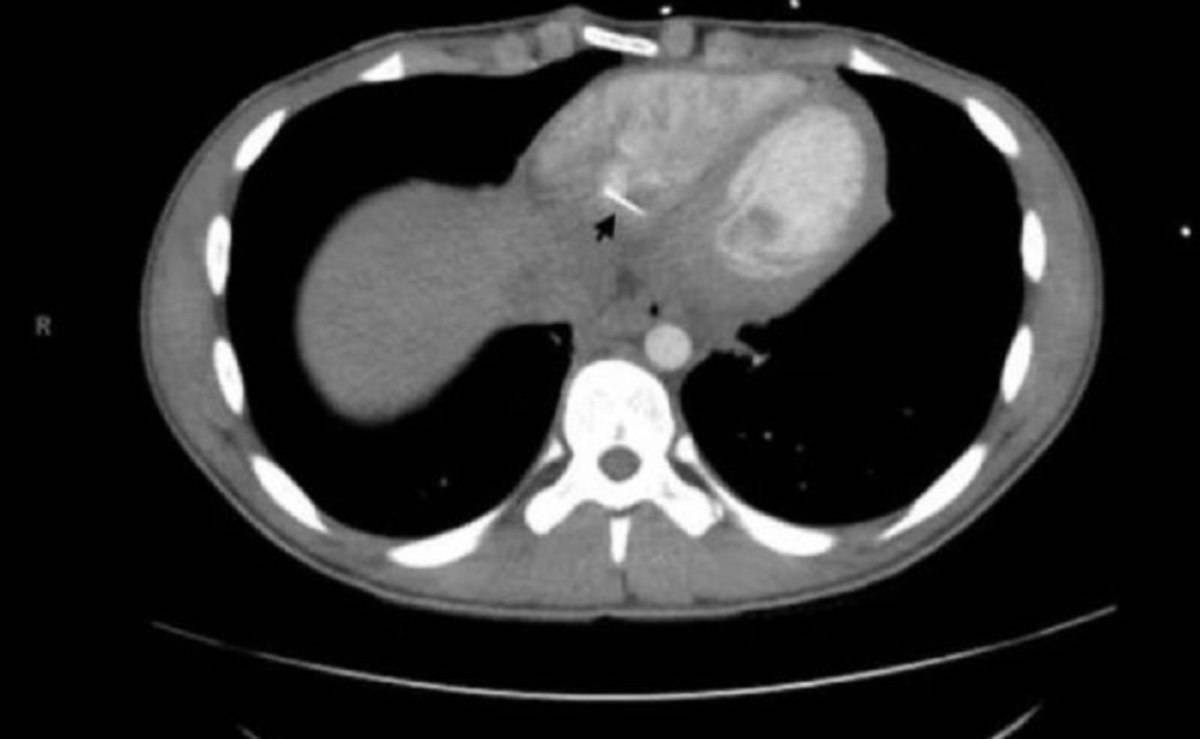

Forti dolori al Petto: in ospedale la scoperta shock

Un ragazzo di 17 anni si è presentato in ospedale in ospedale con un grave problema, ma la soluzione è risultata ...